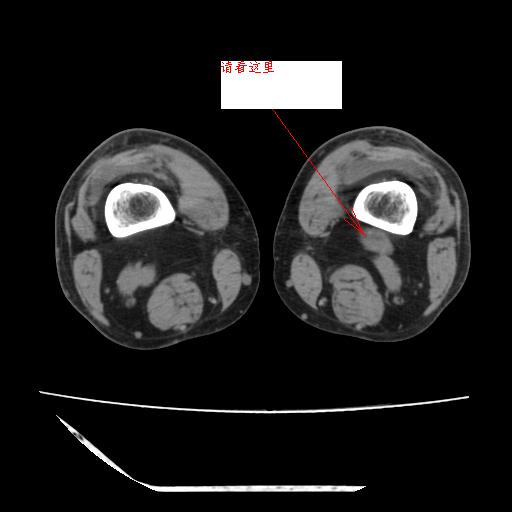

作者: 听蝉观竹 时间: 2008-5-5 05:11

标题: 回复:ct13225:老年男性,左膝关节疼痛数月;请各位老师讨

这是由于两侧的肌肉不对称所致,加上扫描的平面也有些差异。请看示意图:

这个病例诊断:退行性骨关节炎